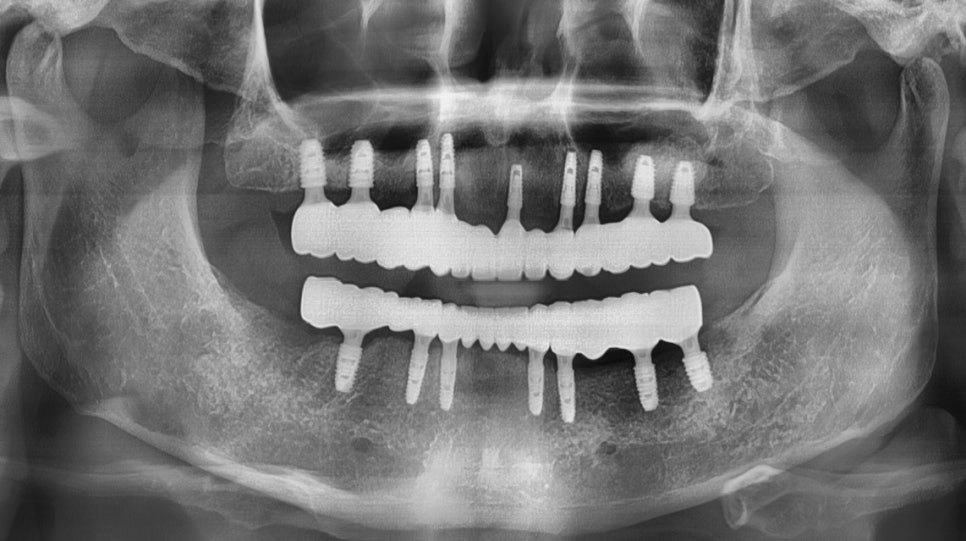

얼마전에 서초동임플란트치과로 내원하신 70대 남성분이십니다.

현재 상태를 파악하기 위해서

우선 3D CT와 x-ray를 통해서

구강 구조물과 상태를 확인하는 과정을 거쳤습니다.

우선 잔존 치아가 거의 없기 때문에

일상에 있어서 불편함을 상당하신 상태였습니다.

CT와 X-ray를 통해서 상악 구치부에 있는

잔존 치조골의 높이와

필요한 뼈이식의 양을 먼저 파악했습니다.

또한 하치조 신경관의 위치를 3D CT로 분석해서

인공치아가 식립 될 수 있도록

전체적인 치료계획을 수립했습니다.

하악 CT의 경우 하치조 신경(붉은색 처리된 부분)과의

거리를 분석하여 신경손상이 거의 없도록

미리 예측하고 식립 합니다.